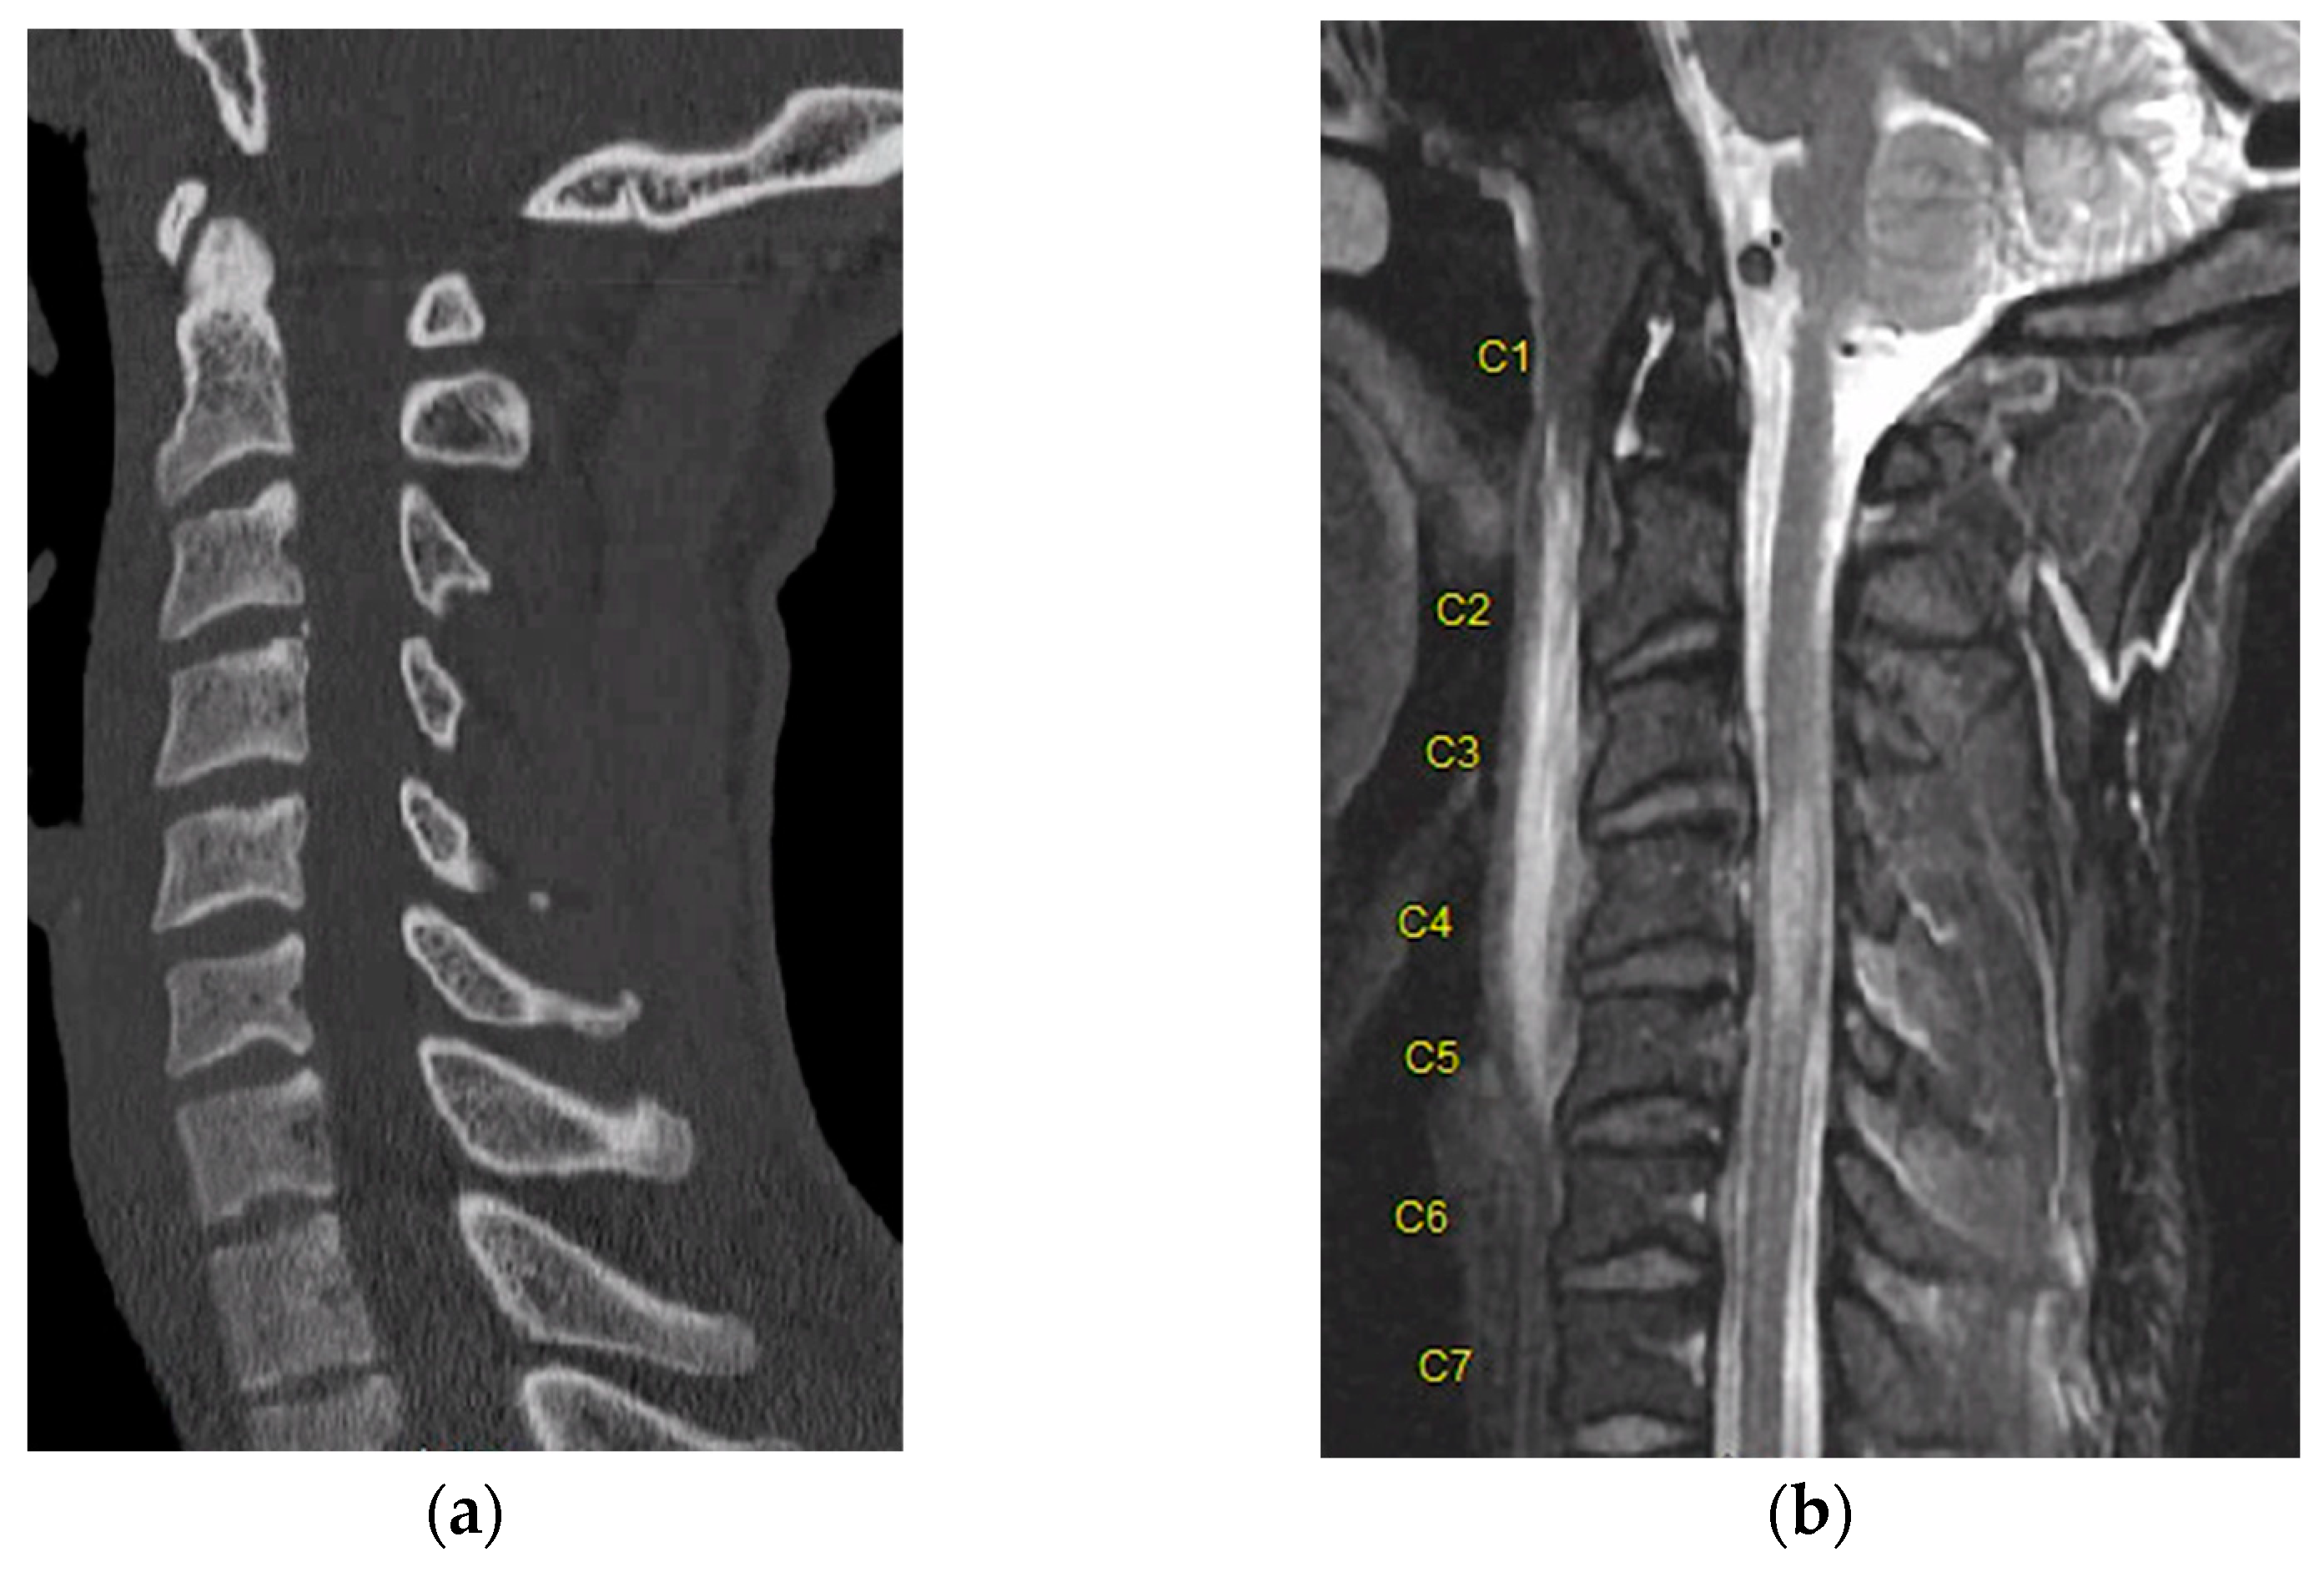

One such example that highlights this comes from our own institution. An adult male patient with no past medical history was brought into our emergency department with negative CT of the entire spine after a rollover motor vehicle crash. Upon initial evaluation, he was displaying clinical signs of spinal cord injury including weakness of the bilateral lower extremities. Thus, MRI was obtained, which demonstrated ligamentous injury and cord signal change (STIR signal) spanning from C3–5 (Figure 3).

Figure 3.

(a) Sagittal CT demonstrating no bony injury or malalignment to a trauma patient. (b) Sagittal MRI STIR sequence demonstrating cord signal change with evidence of contusion spanning from C3–C5. “C1–C7” designate each corresponding spinal level.

This highlights how CT imaging is not without problems, and additionally, that artifacts from image acquisition can occur, such as metal, beam hardening, scatter, and ring artifacts [19]. A combination of advancements in mathematics and technology has allowed for these artefacts to be reduced. For example, photon counting CT has been shown to reduce beam hardening artefact while increasing spatial resolution [13,19]. Additionally, CT does not determine the severity of spinal cord injury, nor does it assist in assessing the prognostication of the injury.